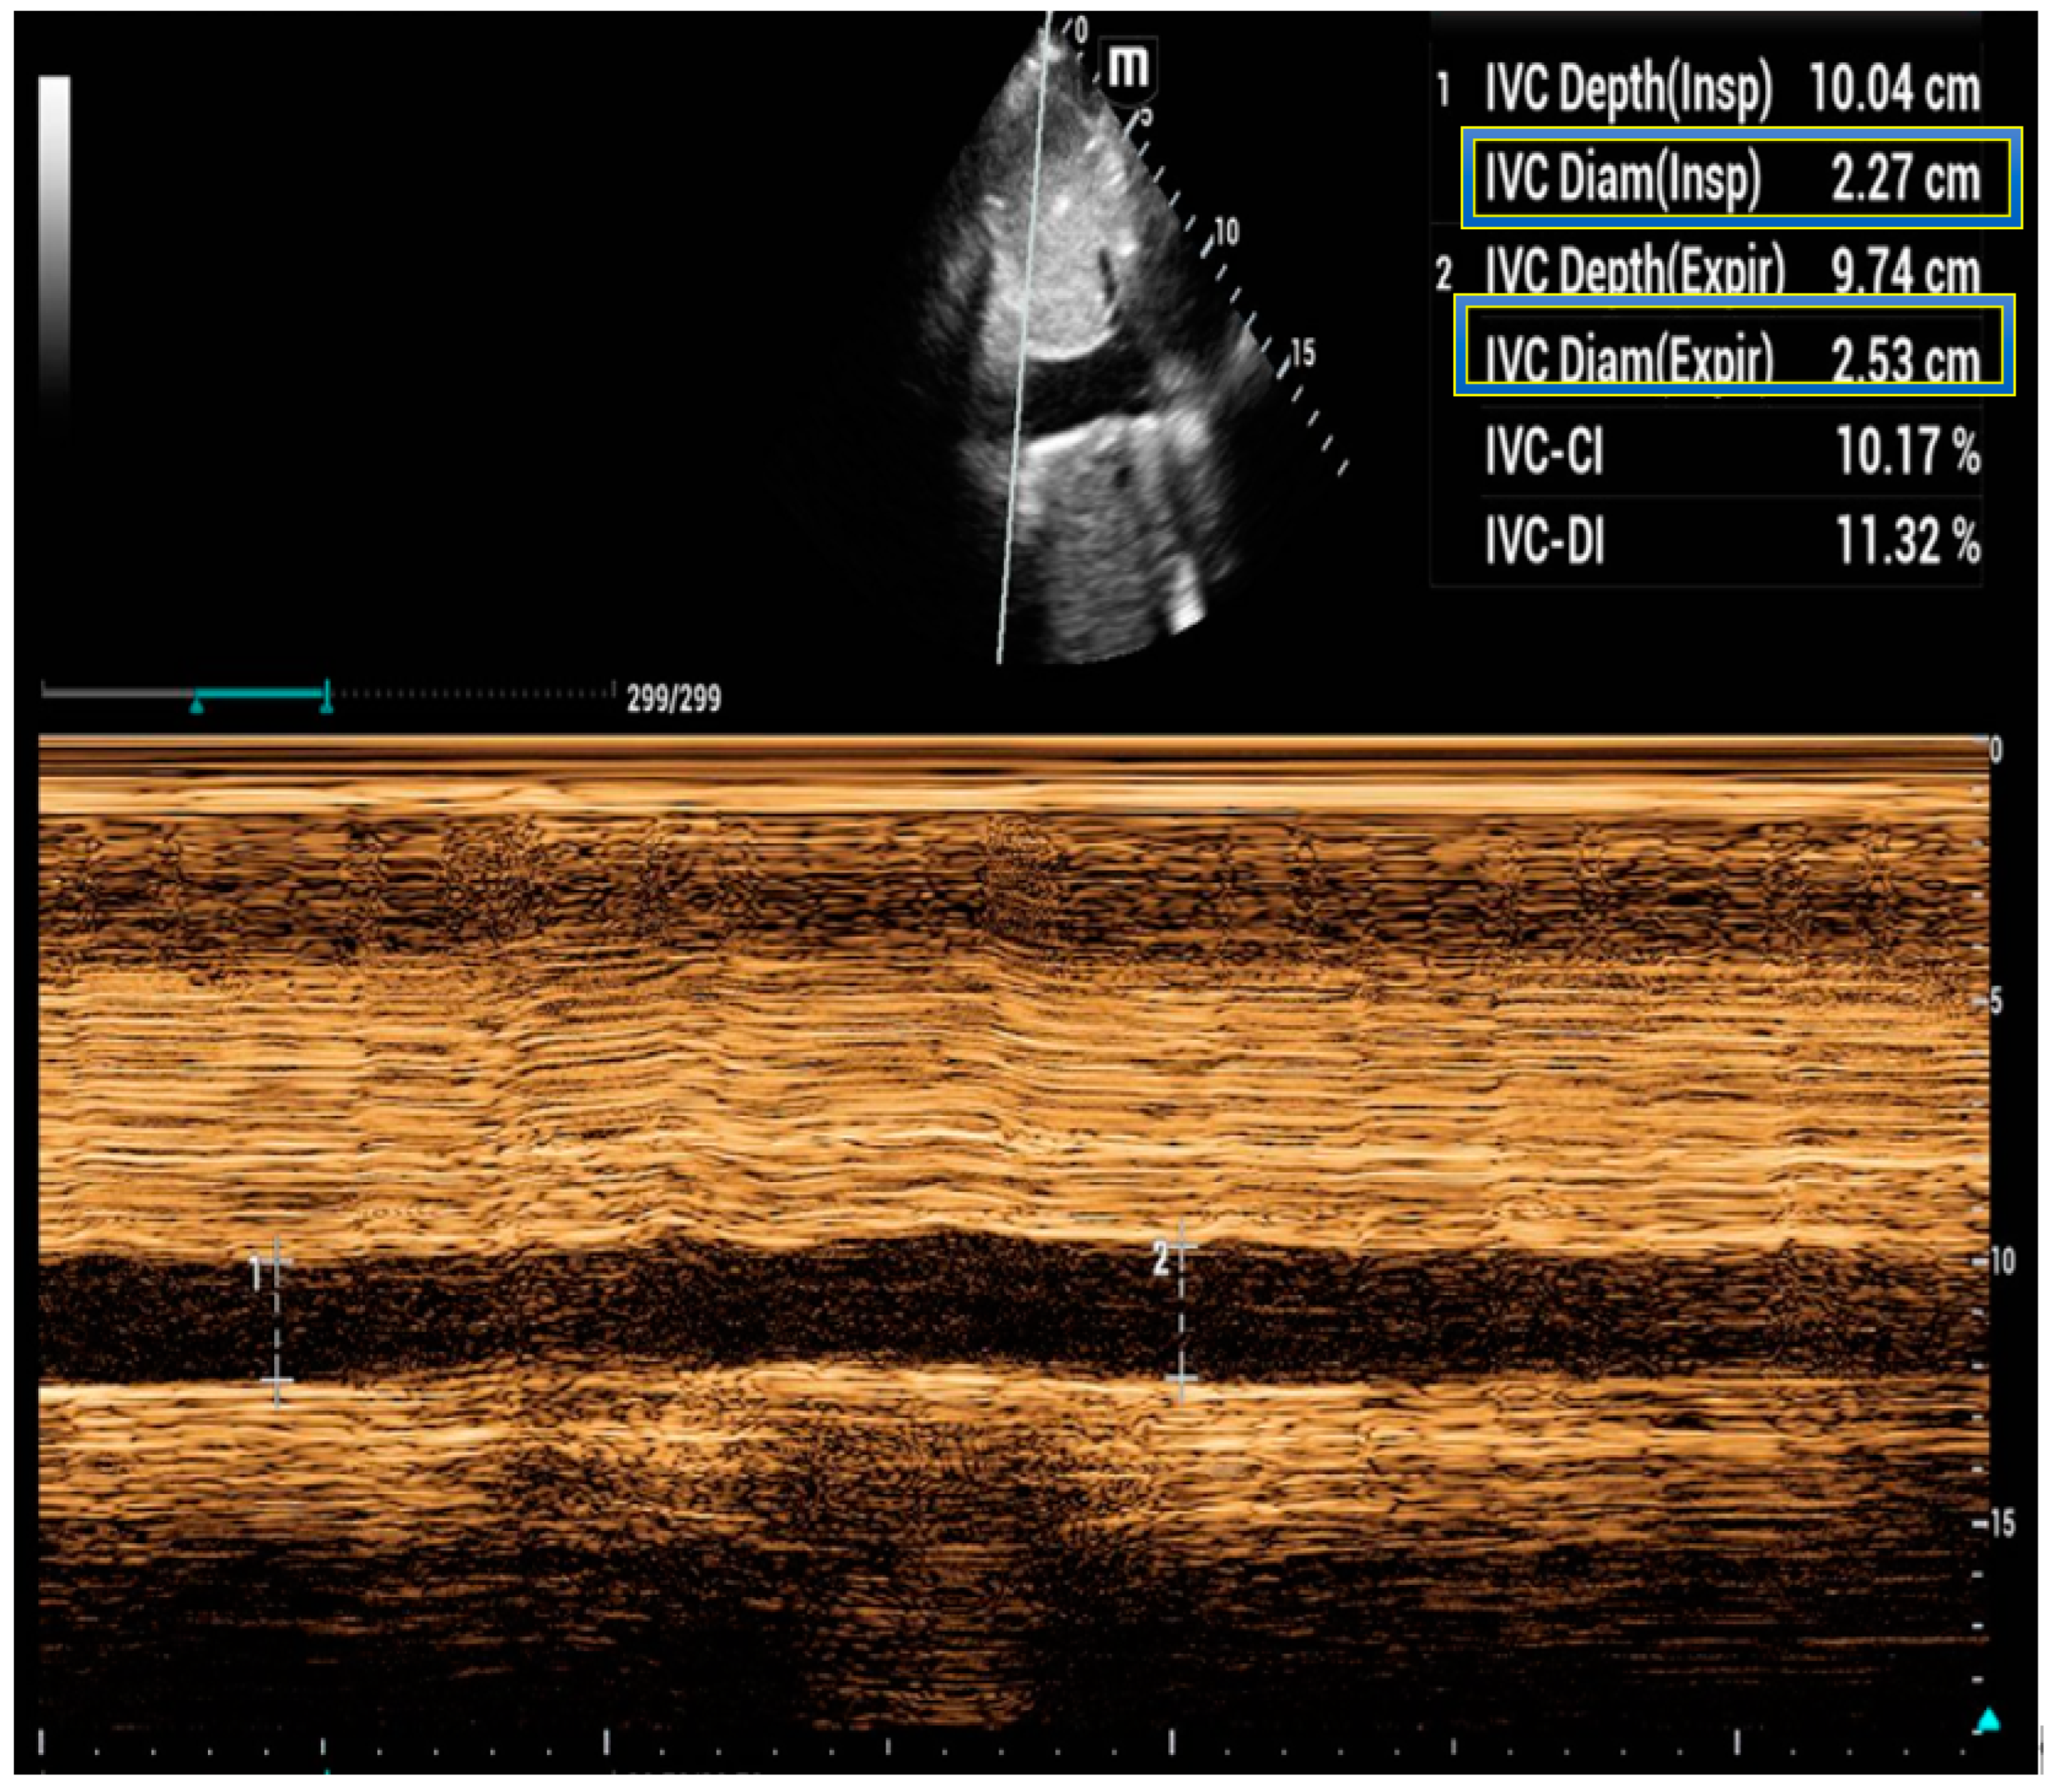

5. Inferior Vena Cava Ultrasound

- Brennan, J.M.; Blair, J.E.; Goonewardena, S.; Ronan, A.; Shah, D.; Vasaiwala, S.; Kirkpatrick, J.N.; Spencer, K.T. Reappraisal of the use of inferior vena cava for estimating right atrial pressure. J. Am. Soc. Echocardiogr. 2007, 20, 857–861. [Google Scholar] [CrossRef]

- Lang, R.M.; Badano, L.P.; Mor-Avi, V.; Afilalo, J.; Armstrong, A.; Ernande, L.; Flachskampf, F.A.; Foster, E.; Goldstein, S.A.; Kuznetsova, T.; et al. Recommendations for cardiac chamber quantification by echocardiography in adults: An update from the American Society of Echocardiography and the European Association of Cardiovascular Imaging. J. Am. Soc. Echocardiogr. 2015, 16, 233–271. [Google Scholar]

- Rudski, L.G.; Lai, W.W.; Afilalo, J.; Hua, L.; Handschumacher, M.D.; Chandrasekaran, K.; Solomon, S.D.; Louie, E.K.; Schiller, N.B. Guidelines for the echocardiographic assessment of the right heart in adults: A report from the American Society of Echocardiography endorsed by the European Association of Echocardiography, a registered branch of the European Society of Cardiology, and the Canadian Society of Echocardiography. J. Am. Soc. Echocardiogr. 2010, 23, 685–713; quiz 686–688. [Google Scholar]

- Feissel, M.; Michard, F.; Faller, J.P.; Teboul, J.L. The respiratory variation in inferior vena cava diameter as a guide to fluid therapy. Intensive Care Med. 2004, 30, 1834–1837. [Google Scholar] [CrossRef]

- Barbier, C.; Loubieres, Y.; Schmit, C.; Hayon, J.; Ricome, J.L.; Jardin, F.; Vieillard-Baron, A. Respiratory changes in inferior vena cava diameter are helpful in predicting fluid responsiveness in ventilated septic patients. Intensive Care Med. 2004, 30, 1740–1746. [Google Scholar] [CrossRef]

- Besli, F.; Kecebas, M.; Caliskan, S.; Dereli, S.; Baran, I.; Turker, Y. The utility of inferior vena cava diameter and the degree of inspiratory collapse in patients with systolic heart failure. Am. J. Emerg. Med. 2015, 33, 653–657. [Google Scholar] [CrossRef]

- Pellicori, P.; Carubelli, V.; Zhang, J.; Castiello, T.; Sherwi, N.; Clark, A.L.; Cleland, J.G. IVC diameter in patients with chronic heart failure: Relationships and prognostic significance. JACC Cardiovasc. Imaging 2013, 6, 16–28. [Google Scholar] [CrossRef] [PubMed]